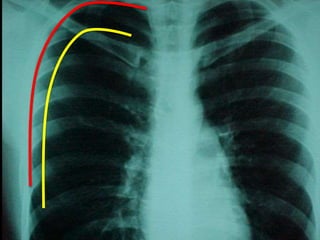

• Diagnóstico

– Radiografia de tórax

• Inspiração profunda (A)

• Expiração profunda

• Diagnóstico – Anamnese –Exame físico – Radiografia de tórax • Inspiração profunda (A) • Expiração profunda – TC de tórax